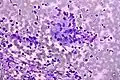

Micrograph of a Field stain showing malignant melanoma.

Field stain is a histological method for staining of blood smears. It is used for staining thick blood films in order to discover malarial parasites. Field's stain is a version of a Romanowsky stain, used for rapid processing of the specimens.[1]

Field's stain consists of two parts - Field's stain A is methylene blue and Azure 1 dissolved in phosphate buffer solution; Field's stain B is Eosin Y in buffer solution. Field stain is named after physician John William Field, who developed it in 1941.[2]